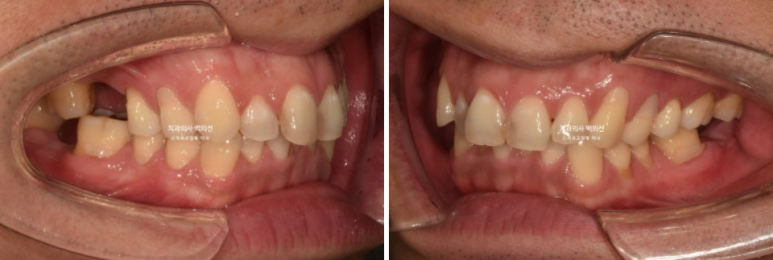

중심선 불일치와 심한 과개교합, 송곳니 덧니 등이 보입니다.

사진에 듬성듬성 보이는 총 3군데의 빈공간은 어금니가 없는 상태입니다.

언젠가는 임플란트를 해야지 하고 없는 채로 시간이 흘러 주변 어금니들이 빈공간으로 쓰러진 상태입니다.